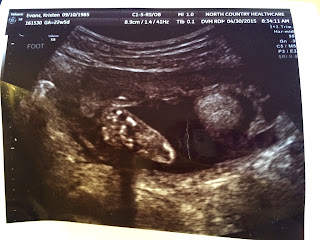

WE ARE HAVING A LITTLE BOY!!!

Everything looked great at the 22 week ultrasound, The little man was being shy and not wanting to show between his legs so it was a challenge to see. He was also squirming around so much the ultrasound tech was having trouble getting pictures! He is measuring in the 75% percentile and I was actually measuring about 5 days ahead of my scheduled due date. Maybe that is why I feel like I suddenly popped and am much bigger than with Ember :)

Here are some of the ultrasound pictures!!